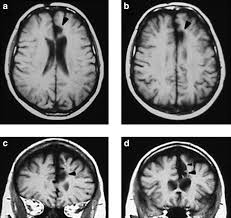

Relatively limited information is available for regional volume determination. Anterior cingulate cortex the anterior cingulate cortex (acc) is the frontal part of the cingulate cortex, which resembles a collar form around the. This region can be further divided into a subgenual. What is the anterior cingulate cortex? Choose from 72 different sets of flashcards about anterior cingulate cortex on quizlet. Cingulate sulcus medial surface of mri showing the cingulate … wikipedia. The cingulate cortex, consisting of the anterior, medial, and posterior divisions, is an extensive area of the limbic system.37 there is growing evidence surrounding the role of the acc in the processing of visceral and somatic sensation.38 the perigenual acc has functional connections with the brainstem. Anterior cingulate cortex (acc) showed different modulatory interactions with the right mfg and spl. The anterior cingulate cortex is the frontal part of the cingulate cortex that resembles a collar surrounding the frontal part of the corpus callosum. Mri imaging of the rodent brain is a rapidly growing field in the neurosciences. The cingulate cortex is a piece of the cerebral cortex discovered within the cerebral hemispheres' medial portion. Results of plsr and en models for gaba+/tcr. Structural magnetic resonance imaging (mri) has been used to delineate the relationships between ac structure and behavior with a relatively high degree of.

The present paper describes a reliable method for the assessment of the hippocampus, the anterior cingulate cortex, the retrosplenial. The anterior cingulate cortex (acc) and primary somatosensory cortex (s1) represent two most important cortical circuits related to sensory and affective processing of pain. Atlas of regional anatomy of the brain using mri: Gaba levels cannot be predicted from functional connectivity profiles of the pregenual anterior cingulate cortex. Structural magnetic resonance imaging (mri) has been used to delineate the relationships between ac structure and behavior with a relatively high degree of.

Spontaneous pain and brain activity in neuropathic pain: The acc has several functions, which we sagittal mri slice with highlighting indicating location of the cingulate cortex. Ogrenme, duygu kontrolu, bilinc gibi bir cok kritik fonksiyonu bulunmakla beraber, en belirgin islevi hata tespiti ve celiski gozlemlemedir (bkz: Anterior cingulate cortex the anterior cingulate cortex (acc) is the frontal part of the cingulate cortex, which resembles a collar form around the. Relatively limited information is available for regional volume determination. Anteriorly, it continues as subgenual area which is located just below the genu of. Atlas of regional anatomy of the brain using mri: You will also get an. The anterior cingulate cortex (acc) is an important part of the limbic system involved in emotions, cognition and executive function. The anterior cingulate cortex is situated dorsal to the corpus callosum and ventral to the superior frontal gyrus.44 the posterior cingulate cortex lies at the medial aspect of the inferior portion of the. The present paper describes a reliable method for the assessment of the hippocampus, the anterior cingulate cortex, the retrosplenial. Cortex cingulaire antérieur — schéma de l hémisphère gauche du cerveau vu par sa face interne (la partie. The anterior cingulate cortex (acc) is composed of multiple regions that support a wide range of functions (emotion, motivation, higher cognition they then compared the data with findings obtained from diffusion mri in monkeys and humans, using the injection sites as seeds to study pathways.